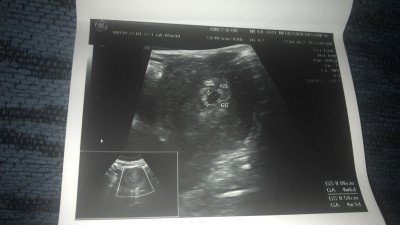

Dün keseyi görmek için gittim şükür gözüktü ama doktor kese boyutu ya da ultrasona göre kaç haftalık gibi şeyleri söylemedi bende sormayı unuttum anlayan varsa bana yorumlayabilir mi. GS kese boyutuymuş ama 2 defa yazıyor GA bebeğin kaç haftalık olduğunu o da 2 tane yazıyor anlamadım. Ya da kesenin yeri nasıl duruşu gibi şeyleri

4 hafta 6 günlük yazıyor canım daha çok küçük

Hem 4+3 hem 4+6 diyor niye 2 tane

Biri gelişimşdir biri döllenme zamanıdır

Biri adet tarihine göre kaç haftalık olduğu diğeri gerçekte kaç haftalık olduğu

Biri kesenin ölçüsü diğeri bebeğin. Sıkıntı olsaydı doktor söylerdi. Demekki sıkıntı yokmus :) ve bu erkek olacak gibime geldi. Hayırlı olsun

Ah şimdi daha dikkatli baktımda, haftanız daha cooooook erken. Bebek gözükmüyor bile. Keseye göre ölçüm yapmış. 6/7 haftalarda gidilir normalde ilk, siz baya erkencisiniz :))

4+3 haftalık sağlıkla al kucağına inşallah

Sağol canım benim niye biri 4+6 diğeri 4+3 üstteki 5+1 adet tarihime göre